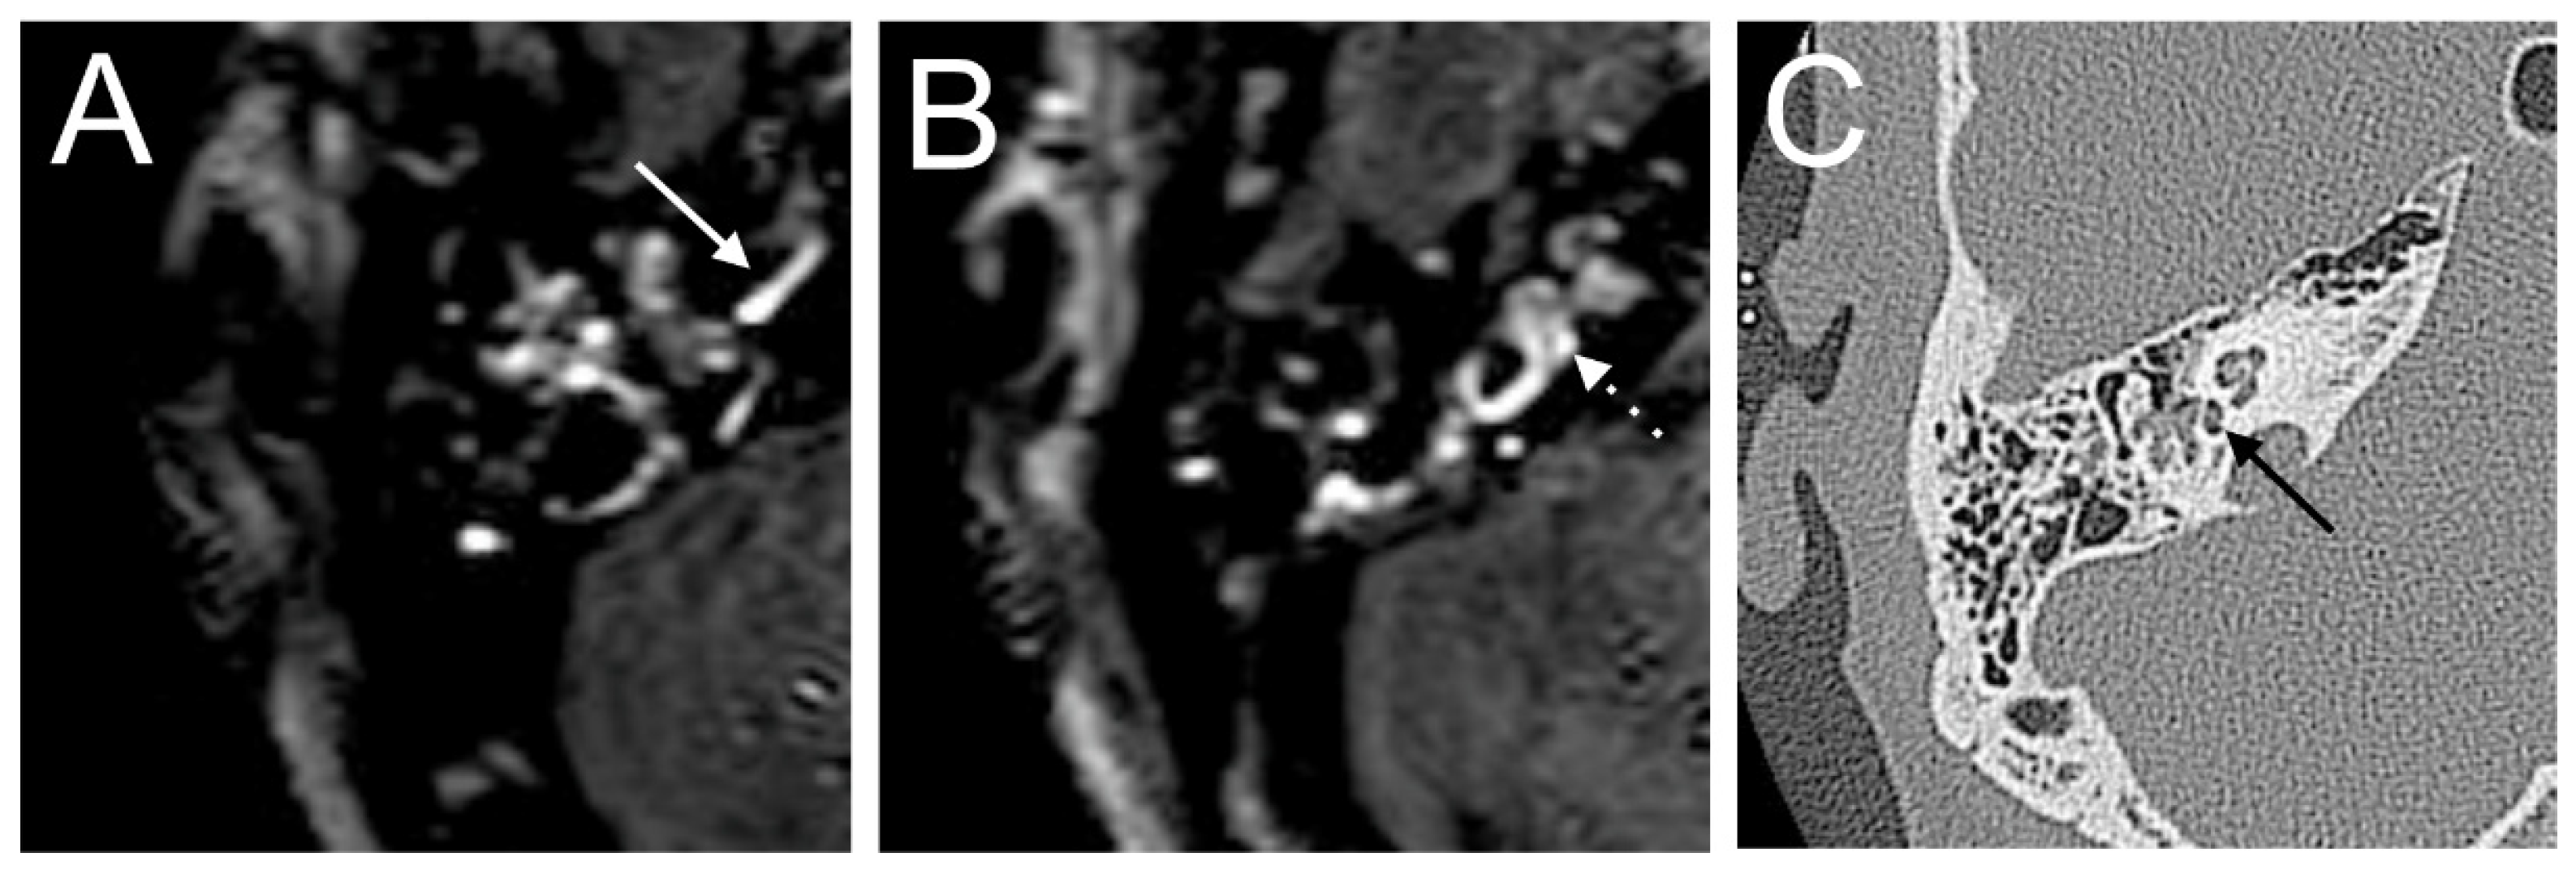

A 60-year-old male presented with a sudden hearing loss on the right side for one week. The PTA was 110 dB on the right side. The patient had already had a sudden hearing loss on the same side in history, which was recovered. He denied having any other symptoms, such as tinnitus, vertigo, or aural fullness. He already had a cochlear implant on the left side related to sensorineural hearing loss. The visual examination showed a spontaneous nystagmus to the left side. A right-side hyporeflexia was observed in the caloric test. The VHIT test revealed a decreased right anterior (0.00) VOR gain. Intraoperatively, a PLF track around the RW niche was observed. The CTP test on the right side was positive, suggesting a PLF. On the 4 h delayed 3D-FLAIR image, a cochlear and vestibular contrast enhancement on the side of hearing loss was found (Figure 1). However, about 3/3 of fluid filling in the RW niche was observed in the affected ear in the CT, which could not be confirmed on T2W MRI. Additionally, the mesotympanon, hypotympanon, and mastoid were filled with fluid on the CT. Because of artifacts on the left side after CI, a side-to-side comparison was not possible.

Figure 1. A 60-year-old male presented with a sudden hearing loss on the right side for one week. The axial 4 h delayed 3D FLAIR sequence shows a contrast enhancement in the cochlear basal turn (arrow) (A) and vestibulum (B). About 3/3 of fluid filling in the RW niche was observed (arrow, (C)).